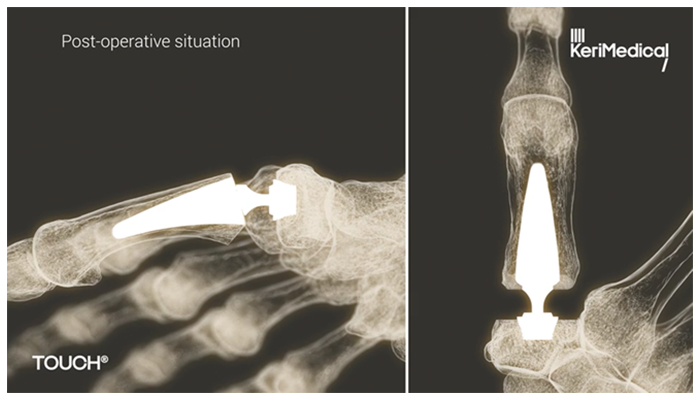

With TOUCH® CMC 1, the surgeon doesn’t remove the bone. Instead, small implants are placed in the trapezium and first thumb bone (metacarpal). Because the trapezium is left in place, the surgery is less traumatic, promoting better stability and recovery. Each implant is customized to the patient, leading to a seamless, natural feel.

See how TOUCH® CMC 1 works.